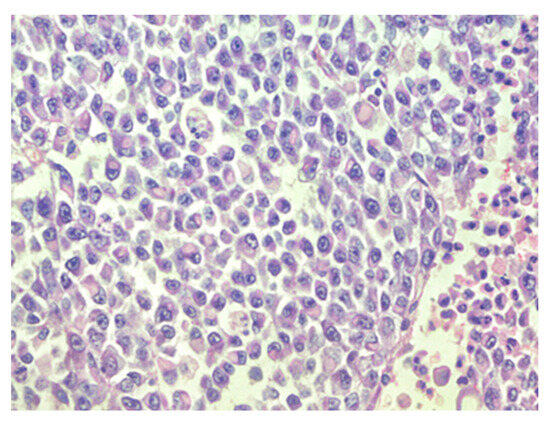

Figure 2.

Sheets of rhabdoid cells with eccentrically located nuclei and eosinophilic cytoplasm, hematoxylin–eosin, original magnification ×400.

The patient was transferred to a neurosurgical facility, where a subsequent right-sided craniotomy with subtotal resection was performed. Total resection was not feasible as the tumor infiltrated the M1 segment of the right middle cerebral artery (MCA). Subsequently, the patient’s condition showed a dynamic improvement, and she started to move her left arm and leg more. The histological picture was consistent with the histology of the classic rhabdoid tumor: a small, round-shaped cell with an eccentrically placed nuclear, dense chromatin pattern, and bright eosinophilic cytoplasm. Immunohistochemical analysis showed retained nuclear expression of INI1, which is not a typical AT/RT finding. The proliferative marker Ki67 reached 90% at a higher concentration of positive cells, suggesting aggressive progression of tumor growth. The antibodies used for immunohistochemistry were sourced from respected suppliers and underwent extensive validation procedures to ensure reliability and specificity. Specifically, INI1 and BRG1 antibodies were obtained from Santa Cruz Biotechnology Company, while antibodies targeting EMA (epithelial membrane antigen), SYN (synaptophysin), GFAP (glial fibrillary acidic protein), S-100 and Ki67 were sourced from Dako Corporation. Additionally, the IDH1 (isocitrate dehydrogenase 1) antibody was obtained from Dianova. The pathological and immunohistochemical analysis of the patient’s surgical specimen is shown in Figure 1, Figure 2, Figure 3, Figure 4, Figure 5 and Figure 6.